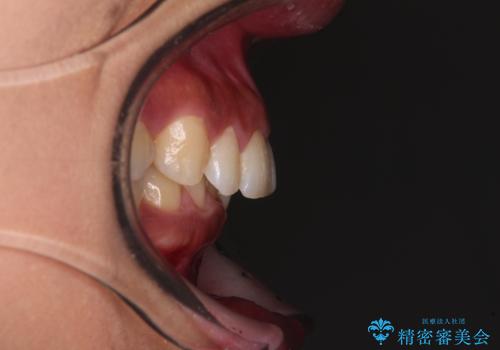

- 下顎前歯部には叢生が認められ、口を自然に閉じにくい状態でした。また、噛み合わせが深い「ディープバイト」の状態で、見た目だけでなく将来的な奥歯への負担も懸念されました。

口元の突出感を改善するため、上下左右の小臼歯4本を抜歯する矯正治療を計画しました。